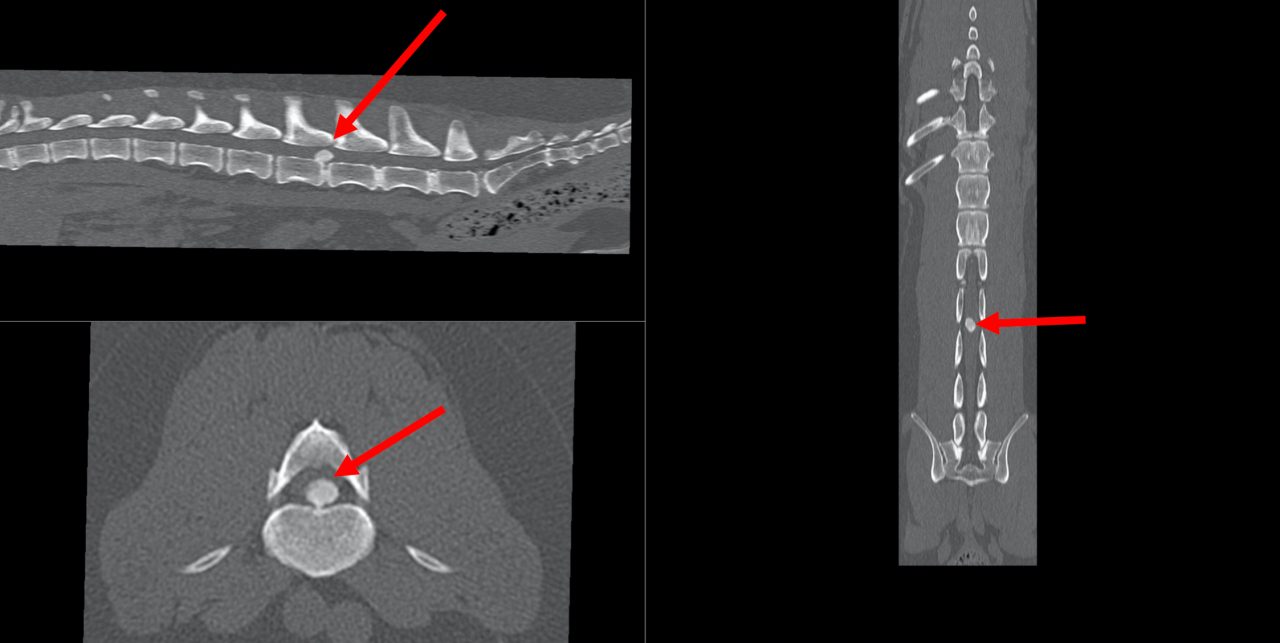

Leider sind auch unsere Haustiere – häufig jüngere kurzbeinige kleine, aber auch große ältere Hunde und selten auch Katzen – von Bewegungsstörungen durch Vorwölbungen der Bandscheibe oder Austritt von Bandscheibenmaterial in Richtung Rückenmark und dessen häutiger sensibler Überzug nicht verschont. Die Folgen sind Schmerzen und Bewegungseinschränkungen bis hin zur vollständiger (Querschnitts-)Lähmung mit Sensibilitätsverlust der Hintergliedmaßen und Funktionsverlust des Harnabsatzes. Da ca. jeder 5. Dackel im Laufe seines Lebens einen Zwischenwirbel-Bandscheibenerkrankung aufweisen kann, heißt diese Erkrankung auch „Dackellähme“. Je nach Schwere der Erkrankung wird eine konservative Therapie (Schmerzmittel und ggf Physiotherapie) oder chirurgische Therapie eingeleitet werden.

Chirurgische dekompressive Eingriffe werden im Bereich der Halswirbelsäule von ventral (untere Halsseite) und im Bereich der Brust-Lendenwirbelsäule von oben (dorsale Laminotomie) oder halbseitlich (Hemilaminektomie) durchgeführt. Im Halsbereich wird ein schmaler Schlitz in den zentralen Bandscheibenbereich gefräst um dann Zugang zum Wirbelkanal zu erhalten und Bandscheibenmaterial zu entfernen und so das Rückenmark zu entlasten. Im Falle einer Bandscheibenextrusion/-protrusion im Brust-Lendenwirbelbereich wird der Zugang zum Rückenmark durch Wegfräsen eines schmalen Schlitzes des Wirbeldaches (siehe Abbildung 2 vor der Operation) oberhalb oder halbseitlich gewählt und unter Schonung des Rückenmarkes  vorsichtig vorgefallenes Bandscheibenmaterial entfernt bzw. die vorgefallene Bandscheibe reduziert (partielle Korpektomie). Danach sollte der Patient innerhalb weniger Tage wieder anfangen, sich schmerzfrei zu bewegen.